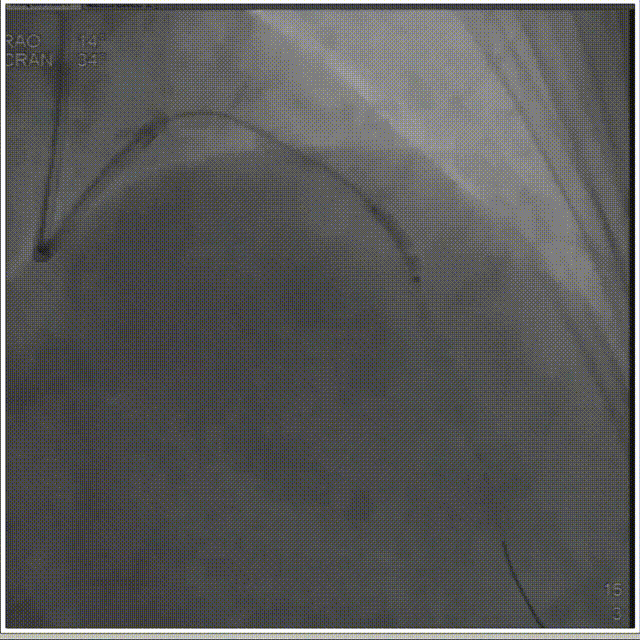

术前造影指示 前降支近、中段严重钙化及狭窄

手术过程中,经2.0mm*15mm 球囊预扩前降支近、中段病变后,使用谱创医疗Sonico-CX 2.5mm*12mm 冲击波球囊置入前降支病变处,先后触发60次冲击波(6个周期,每个周期分别以4 atm 激发冲击波,再以8 atm 扩张成形)实施钙化斑块碎裂术,DSA下可见随着冲击波释放,球囊形状慢慢扩张。谱创医疗Sonico-CX冲击波球囊处理后复查IVUS,显示原钙化环断裂。经过充分的冲击波球囊预处理后,因钙化环得到松解,为进一步扩大管腔面积,用2.5mm *15mm高压球囊进一步扩开前降支近、中段病变,最后顺利放入药物洗脱支架。复查IVUS显示支架膨胀完全、贴壁良好,支架两端未见夹层及血肿,残余狭窄0%,复查造影显示远端血流通畅。